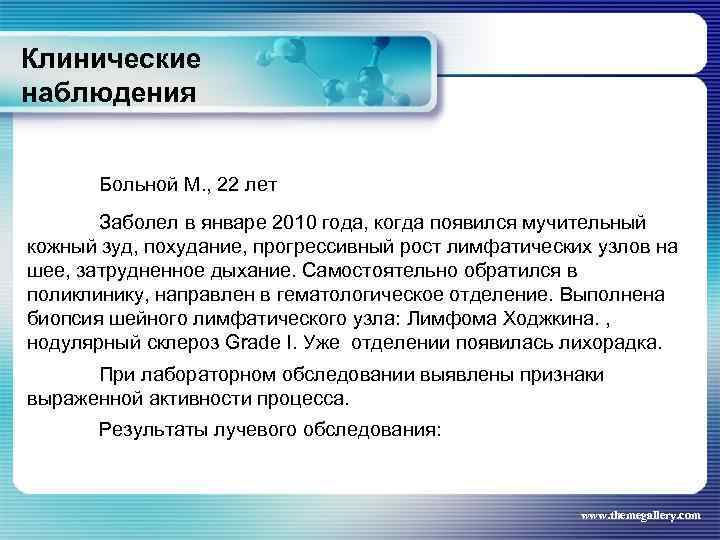

Клинические наблюдения Больной М. , 22 лет Заболел в январе 2010 года, когда появился мучительный кожный зуд, похудание, прогрессивный рост лимфатических узлов на шее, затрудненное дыхание. Самостоятельно обратился в поликлинику, направлен в гематологическое отделение. Выполнена биопсия шейного лимфатического узла: Лимфома Ходжкина. , нодулярный склероз Grade I. Уже отделении появилась лихорадка. При лабораторном обследовании выявлены признаки выраженной активности процесса. Результаты лучевого обследования: www. themegallery. com

Клинические наблюдения Больной М. , 22 лет Заболел в январе 2010 года, когда появился мучительный кожный зуд, похудание, прогрессивный рост лимфатических узлов на шее, затрудненное дыхание. Самостоятельно обратился в поликлинику, направлен в гематологическое отделение. Выполнена биопсия шейного лимфатического узла: Лимфома Ходжкина. , нодулярный склероз Grade I. Уже отделении появилась лихорадка. При лабораторном обследовании выявлены признаки выраженной активности процесса. Результаты лучевого обследования: www. themegallery. com